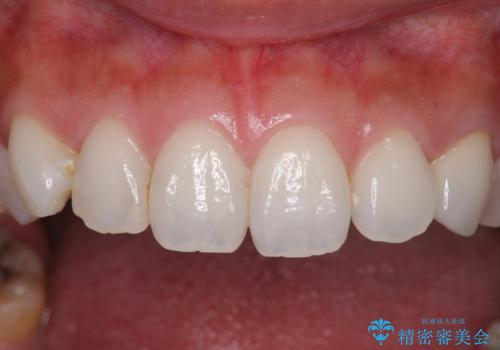

前歯1本の治療では、オールセラミッククラウンといえども周囲と調和しなければ自然な仕上がりにはなりません。

今回は既製の色調のセラミックを選択されましたが、もっと色合いにこだわりたい場合には、オーダーメイドタイプのセラミッククラウンをご選択いただいています。